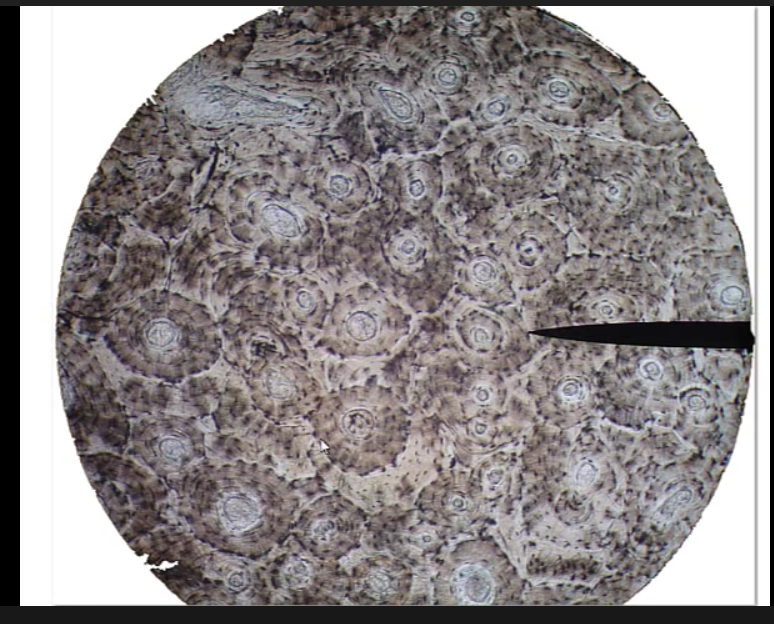

Bone tissue, the circles are called osteons which indicate that this is bone tissue.